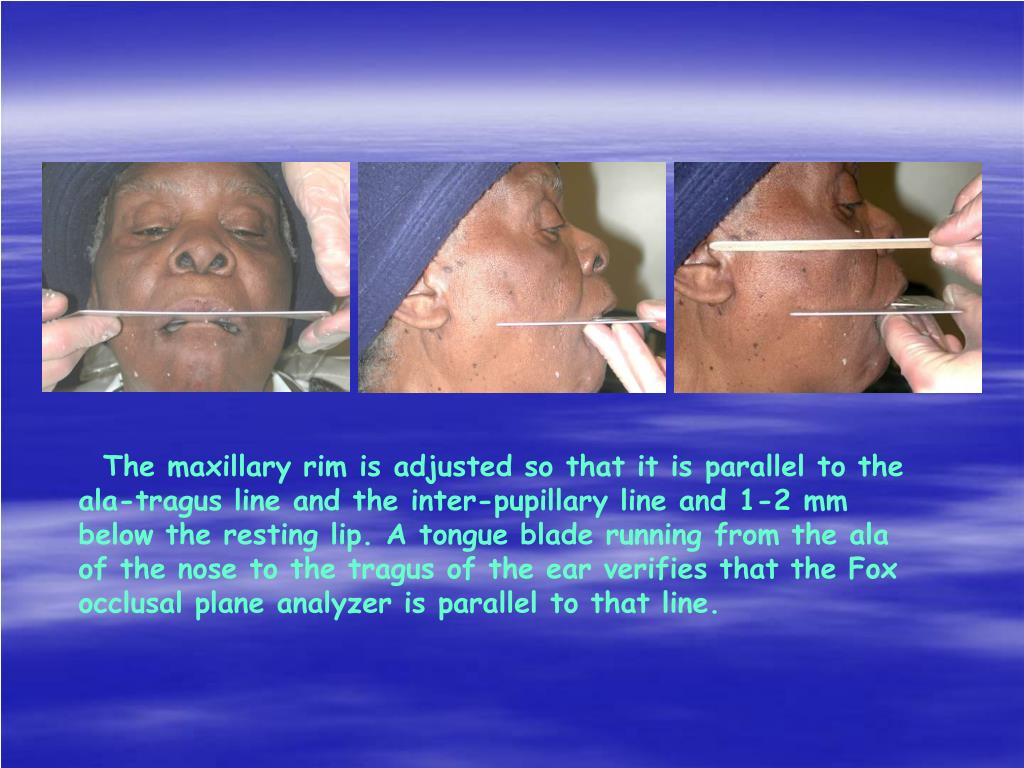

Tragus of the ear must be aligned with the plastic guides ala tragus line should be 50 from level positioning the patient position the patient panoramic lead apron must be used position apron high in front to protect the thyroid apron should be lower in back to expose the neck. Discussion most panoramic x ray machines use the ala tragus line for patient positioning whereas a few use the orbito meatal line. Ala tragus line is one of the common extra oral soft tissue land mark utilized in dental clinics for occlusal plane orientation. Here the occlusal plane should be mildly curved upward to make a smile like line.

The ala tragus line as a guide for orientation of the occlusal plane in complete dentures 1carole abi ghosn 2carla zogheib. The smile line will also be lost. An imaginary plane or line from the ala of the nose to the tragus of the ear. The part of a panoramic x ray machine where the cassette is positioned for exposure.

The angle between this line and the horizontal plane is 3on the panorex and 4on the. Focal trough layer that area between the x ray source and the image receptor that will be imaged distinctly on the panoramic. In other words the ala of the nose should be slightly inferior to the height of the tragus. These zones are as follows.

Important in determining the correct position of the patient s head. Exposure was 80 to 90 kv at 10 ma for 1 5 to 2 seconds in accordance with the subject s physical. The panorex i s. To achieve the correct vertical angulation the head must be positioned upright and symmetrical with the ala of the nose just inferior to the height of the tragus.